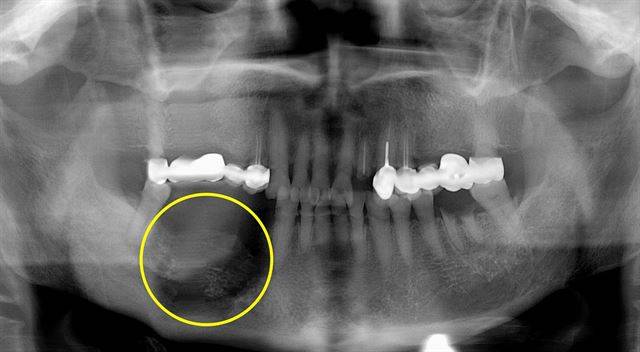

턱뼈가 썩어 무너져 내린 모습.

5년 넘게 골다공증 약을 먹고 있는 황모(70ㆍ여) 씨는 얼마 전 임플란트 시술 때문에 치아를 뽑았는데 잇몸이 붓고 염증이 생겨 병원을 찾았다. 황씨는 골다공증 약인 비스포스포네이트 부작용으로 인해 생기는 '턱뼈괴사증'라는 진단을 받았다. 턱뼈가 썩어 무너져 내리는 무서운 질병이다. 치료를 위해 골다공증 약 복용을 중단했고, 고농도 항생제를 지속적으로 투여해야 했다. 또한 썩어 소실된 턱뼈를 잘라내 뼈 이식 수술을 앞두고 있다.

황씨가 복용한 골다공증 치료제는 '비스포스포네이트' 성분이 포함된 약이다. 값이 싸고 골다공증 예방 효과도 좋아 일반적으로 널리 사용된다. 하지만 최근 이씨처럼 약의 장기 사용에 따른 합병증으로 턱뼈가 썩어 주저앉은 턱뼈괴사증 사례가 늘어나 각별한 주의가 필요하다. 턱뼈괴사증은 일반인에게 아직 낯선 치과질환이다. 세계적으로 2003년에야 첫 환자가 발견됐고, 국내에 알려진 지 몇 년이 되지 않았다.

그러나 오래 복용할 경우 턱뼈가 파괴되는 후유증이 생길 수 있다는 사실이 최근 알려지기 시작했다. 턱뼈는 하루에도 엄청난 양의 세포가 만들어지고 없어지는 활동성이 많은 조직인데 비스포스포네이트 성분의 부작용으로 인해 턱뼈의 흡수와 생성의 균형이 깨지면서 발치, 잇몸질환, 충치, 임플란트 시술 등 턱뼈 노출에 의한 염증이 생겨 치료가 되지 않고 턱뼈가 노출된 상태로 두 달 정도 경과하면 턱뼈까지 썩게 된다.

이처럼 비스포스포네이트로 인해 턱뼈 조직이 죽으면 이를 뽑아도 뽑은 자리가 아물지 않고 병균이 감염돼 수개월에서 수년간 고름이 나오기도 한다. 약을 먹고 썩어 있는 뼈를 제거하고 다듬어도 턱뼈 전체가 괴사됐다면 도려낸 자리가 아물지 않아 턱뼈를 모두 제거할 수도 있다. 특히 일단 약이 인체 내 축적되면 턱뼈 괴사 위험군으로 분류되므로 치아를 뺄 수도 없고 임플란트도 할 수 없게 된다.